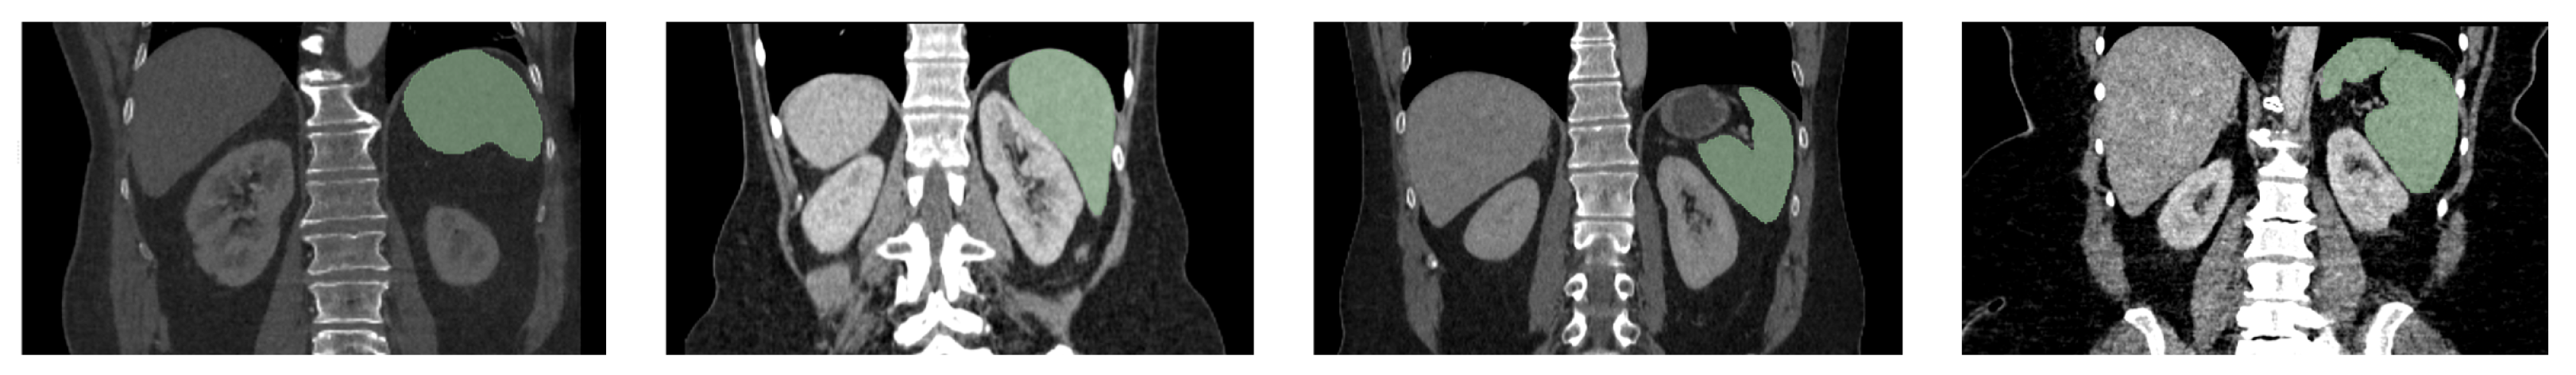

5.1.2. Hospital Dataset

5.5.2. Evaluation on the Hospital Dataset

| Metric | Liver | Spleen | R Kidney | L Kidney | Mean |

|---|---|---|---|---|---|

| DSC | 90.62 | 79.86 | 79.87 | 78.21 | 82.14 |

| IoU | 84.18 | 72.45 | 71.75 | 71.27 | 74.91 |

| HD | 7.77 | 6.84 | 14.85 | 9.88 | 9.84 |